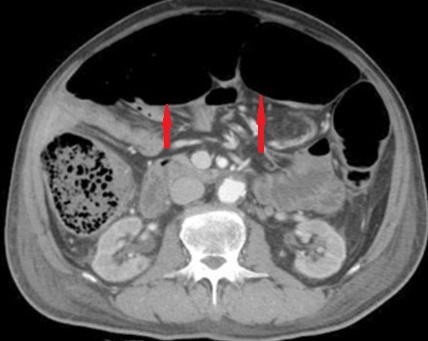

CT scan κοιλίας. Παρουσία ασβεστώσεων, κυστικο-συμπαγών περιοχών και λιπώδους ιστού, ενδεικτικά τερατώματος δεξιάς πλευράς (Ευγενική παραχώρηση Dr. V. Penopoulos)